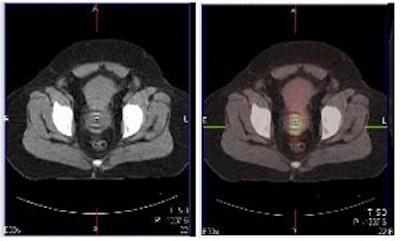

| Above and below, representative images of a 39-year-old patient, currently undergoing treatment, with FIGO stage IB2 squamous cell carcinoma of the cervix. Pretreatment FDG-PET/CT identified an FDG-avid cervical tumor mass plus bilateral iliac and right common iliac metastatic lymphadenopathy. Images courtesy of Dr. Julie Schwarz, Ph.D. |